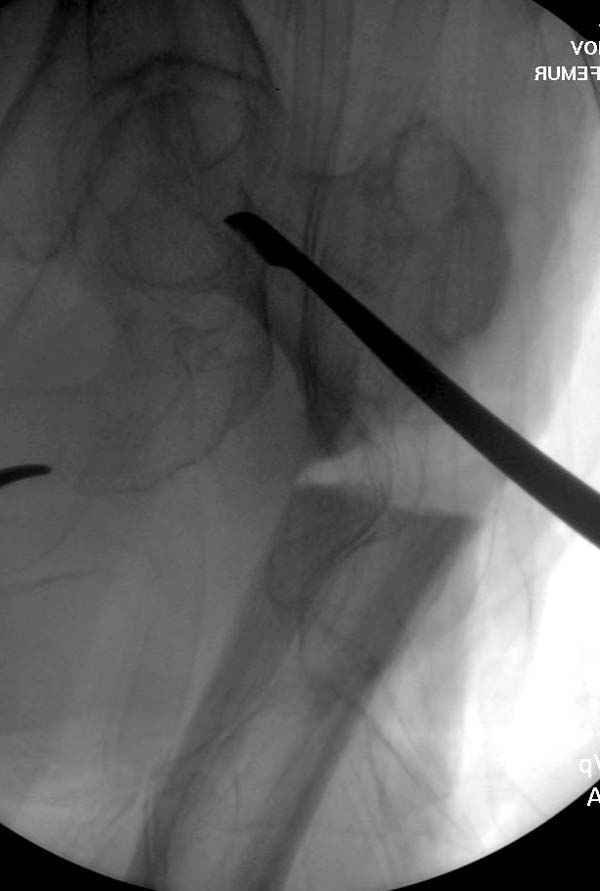

77 летняя больная направлена в нашу клинику на дальнейшее лечение. Из истории, травму получила в сентябре 2007 года и по поводу перелома шейки бедра больная была проперирована тремя каннюлированными шурупами с явным нарушением технологии установки шурупов. Внизу вместо одного шурупа имеется два, что привело к стрессу латерального кортекса. Через месяц по поводу ятрогенного подвертельного перелома сделана фиксация длинной Гамма 3. Установлен без проксимальной блокировки? (set screw). В данный момент имеется несостоятельность конструкции и ложный сустав. Передвигается с помошью костылей, конечность укорочена на 2 см. Какие будут рекомендации?Djoldas Kuldjanov, MDDepartment of Orthopedic SurgerySt. Louis University Medical Center